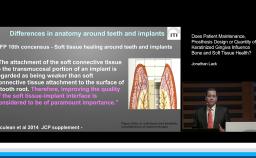

The management of complications with dental implants and implant prostheses is a part of clinical practice today. To reduce the risk for biological, technical or mechanical complications as much as possible, it is important to follow scientific and/or clinical evidence when planning, designing and performing implant prosthodontics dental rehabilitations.

This lecture addresses a number of frequently asked questions in the field and attempts to provide evidence based answers to them. They include the (minimal) number of implants, implant selection, safety and efficacy of short implants, single unit or splinted restorations, implant-tooth connections, cantilevers, type of retention, and material choice.